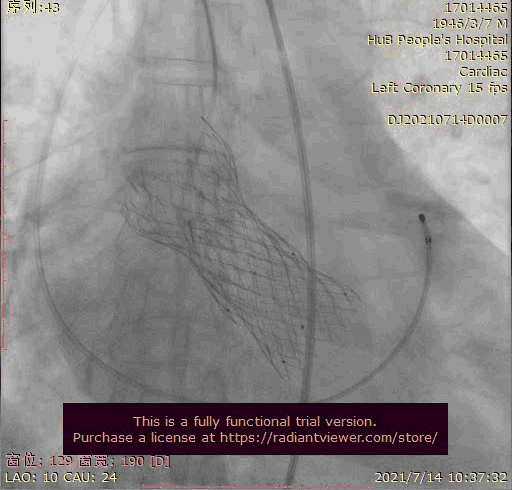

瓣膜稍高位释放

瓣膜位置稍深

使用venus-A plus回收后重新定位释放

瓣膜位置尚可

大结构瓣膜稳定性差,输送器使瓣膜跳到瓣上

奇思妙想使用射频消融大头压住支架至窦底

在大头压迫支架下释放第二个瓣膜

第二个支架完美释放固定第一个支架

术后基本无返流

1.在第一次释放瓣膜时,由于患者主动脉根部瓣上瓣下均比瓣环平面大,受到血流的冲击,瓣膜滑至较深的位置,使用venus-A PLUS回收

2.回收后重新定位释放,由于第一次滑至较深,第二次稍微卸力后瓣膜跳至窦上,使用venus-A PLUS回收,再次重新定位

3.第三次释放瓣膜后位置的把控非常精准,瓣膜位置合适,但由于稳定性差,撤出输送系统时瓣膜跳至窦上,此时非常凶险,瓣膜无法固定住,受到血流的冲击,可能对升主造成夹层的风险,一般会选择开胸取出,但风险非常,在江洪教授的思考下和团队的讨论下,决定使用射频消融大头穿过支架网孔使瓣膜到窦底固定,在此基础上释放第二个瓣膜,使用第二个瓣膜花冠固定住第一个瓣膜

4.第四次瓣膜释放后两个瓣膜均稳定住,造影超声评估无瓣周漏,二尖瓣反流也基本消失,观察一小时后,无其他情况。患者顺利下台